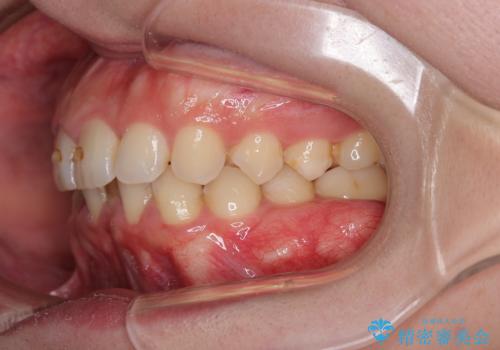

- 下の歯のがたつきを主訴に来院されました。

下の歯のがたつきと右の奥歯の噛みあわせ改善するために治療計画を立てることにしました。

右側臼歯部の咬合改善のために、臼歯部のみ部分的なワイヤー矯正を行い、咬合改善がみられてからインビザラインにて全体的な矯正を行なっていく治療計画を立てました。

噛み合わせをよくするために、ワイヤー矯正とインビザライン矯正のどちらの期間も必要な箇所にゴム掛けを行いながら治療を行いました。

下の前歯のがたつき改善にはIPR(歯と歯の間を削る処置)を行いました。

ゴム掛けを頑張っていただいたので、噛みあわせも改善され綺麗な歯並びになりました。